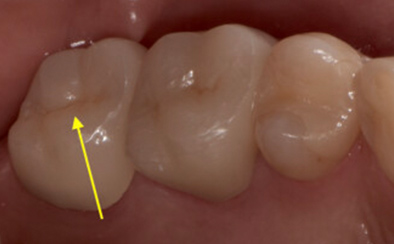

治療前

治療後

黄色い矢印の歯が治療前の対象歯です。レントゲンで観察すると、歯の根のお薬が充分には入っていないようです。

麻酔をして歯の中をマイクロスコープで観察すると、元々あった3つの根だけでなく「もう一つの4番目の根」があったのです。根管治療自体は容易に行えましたが、歯の中を明るく拡大できるマイクロスコープを持っていない歯医者さんでは見つけるのが困難だと思われます。この4つ目の歯の根を治療することにより痛みは消失し「抜歯してインプラント」になるという悪循環に陥らず済みました。根管治療はマイクロスコープを使って精密に、また丁寧に行えば歯を長く保たせることができる治療です。やはり神経自体を残すという選択が、歯の保存にとって一番良いということは間違いありません。

| 費用 | デンタルドック:55,000円 根管治療(奥歯):176,000円 MTAセメント:33,000円 歯の土台:33,000円 合計:297,000円 |

| リスク・副作用 | 治療中に一時的な咬合痛や冷温水痛、若干の歯肉の腫れ、発赤などを生じることがあります。また仮歯の時期には仮歯の脱離や破損の可能性、舌感などに違和感を覚えることがありますが、本歯に移行するまでに通常消失します。 ※すべて症例による違いや個人差があります。 |

※表示金額は全て税込みです。